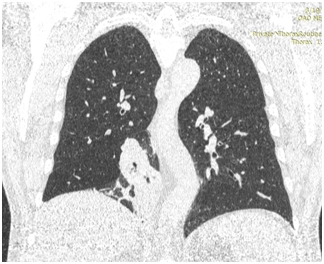

КТ ОГП 06.01.2017. КТ-картина внутрипросветного патологического мягкой плотности компонента (центральный рак?) в промежуточном бронхе правого легкого с ателектазом нижней доли. Лимфаденопатия правого корня, количественная лимфаденопатия средостения.

КТ ОГК от 28.03.2017. По сравнению с предыдущим КТ от 06.01.2017 отмечается выраженная положительная динамика изменений за счет отсутствия образования в просвете промежуточного и нижнедолевого бронхов справа, отсутствия ателектаза нижней доли, а также умеренного уменьшения в количестве и размерах лимфатических узлов средостения и корня правого легкого.